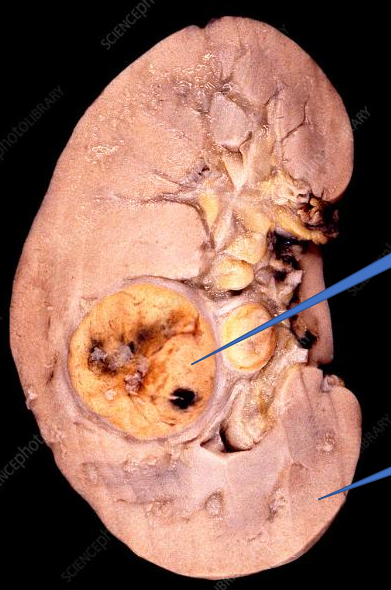

1- renal tumor

2- Normal kidney